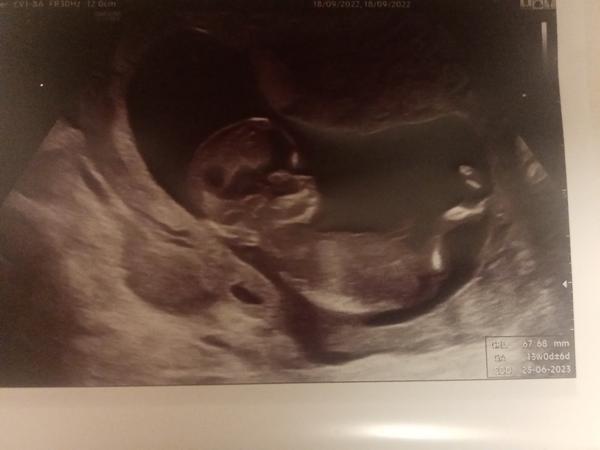

poznáte pohlaví z fotky?

Foto ze screeningu 13+0.

Lékaře jsem se neptala, pohlaví nevíme, jen mě tak napadlo se zeptat.

A dle čeho se pozná konkrétně třeba tady na té fotce? Jestli teda poznat vůbec jde.

z této fotky pohlaví posoudit nelze. Daná oblast není zachycena.